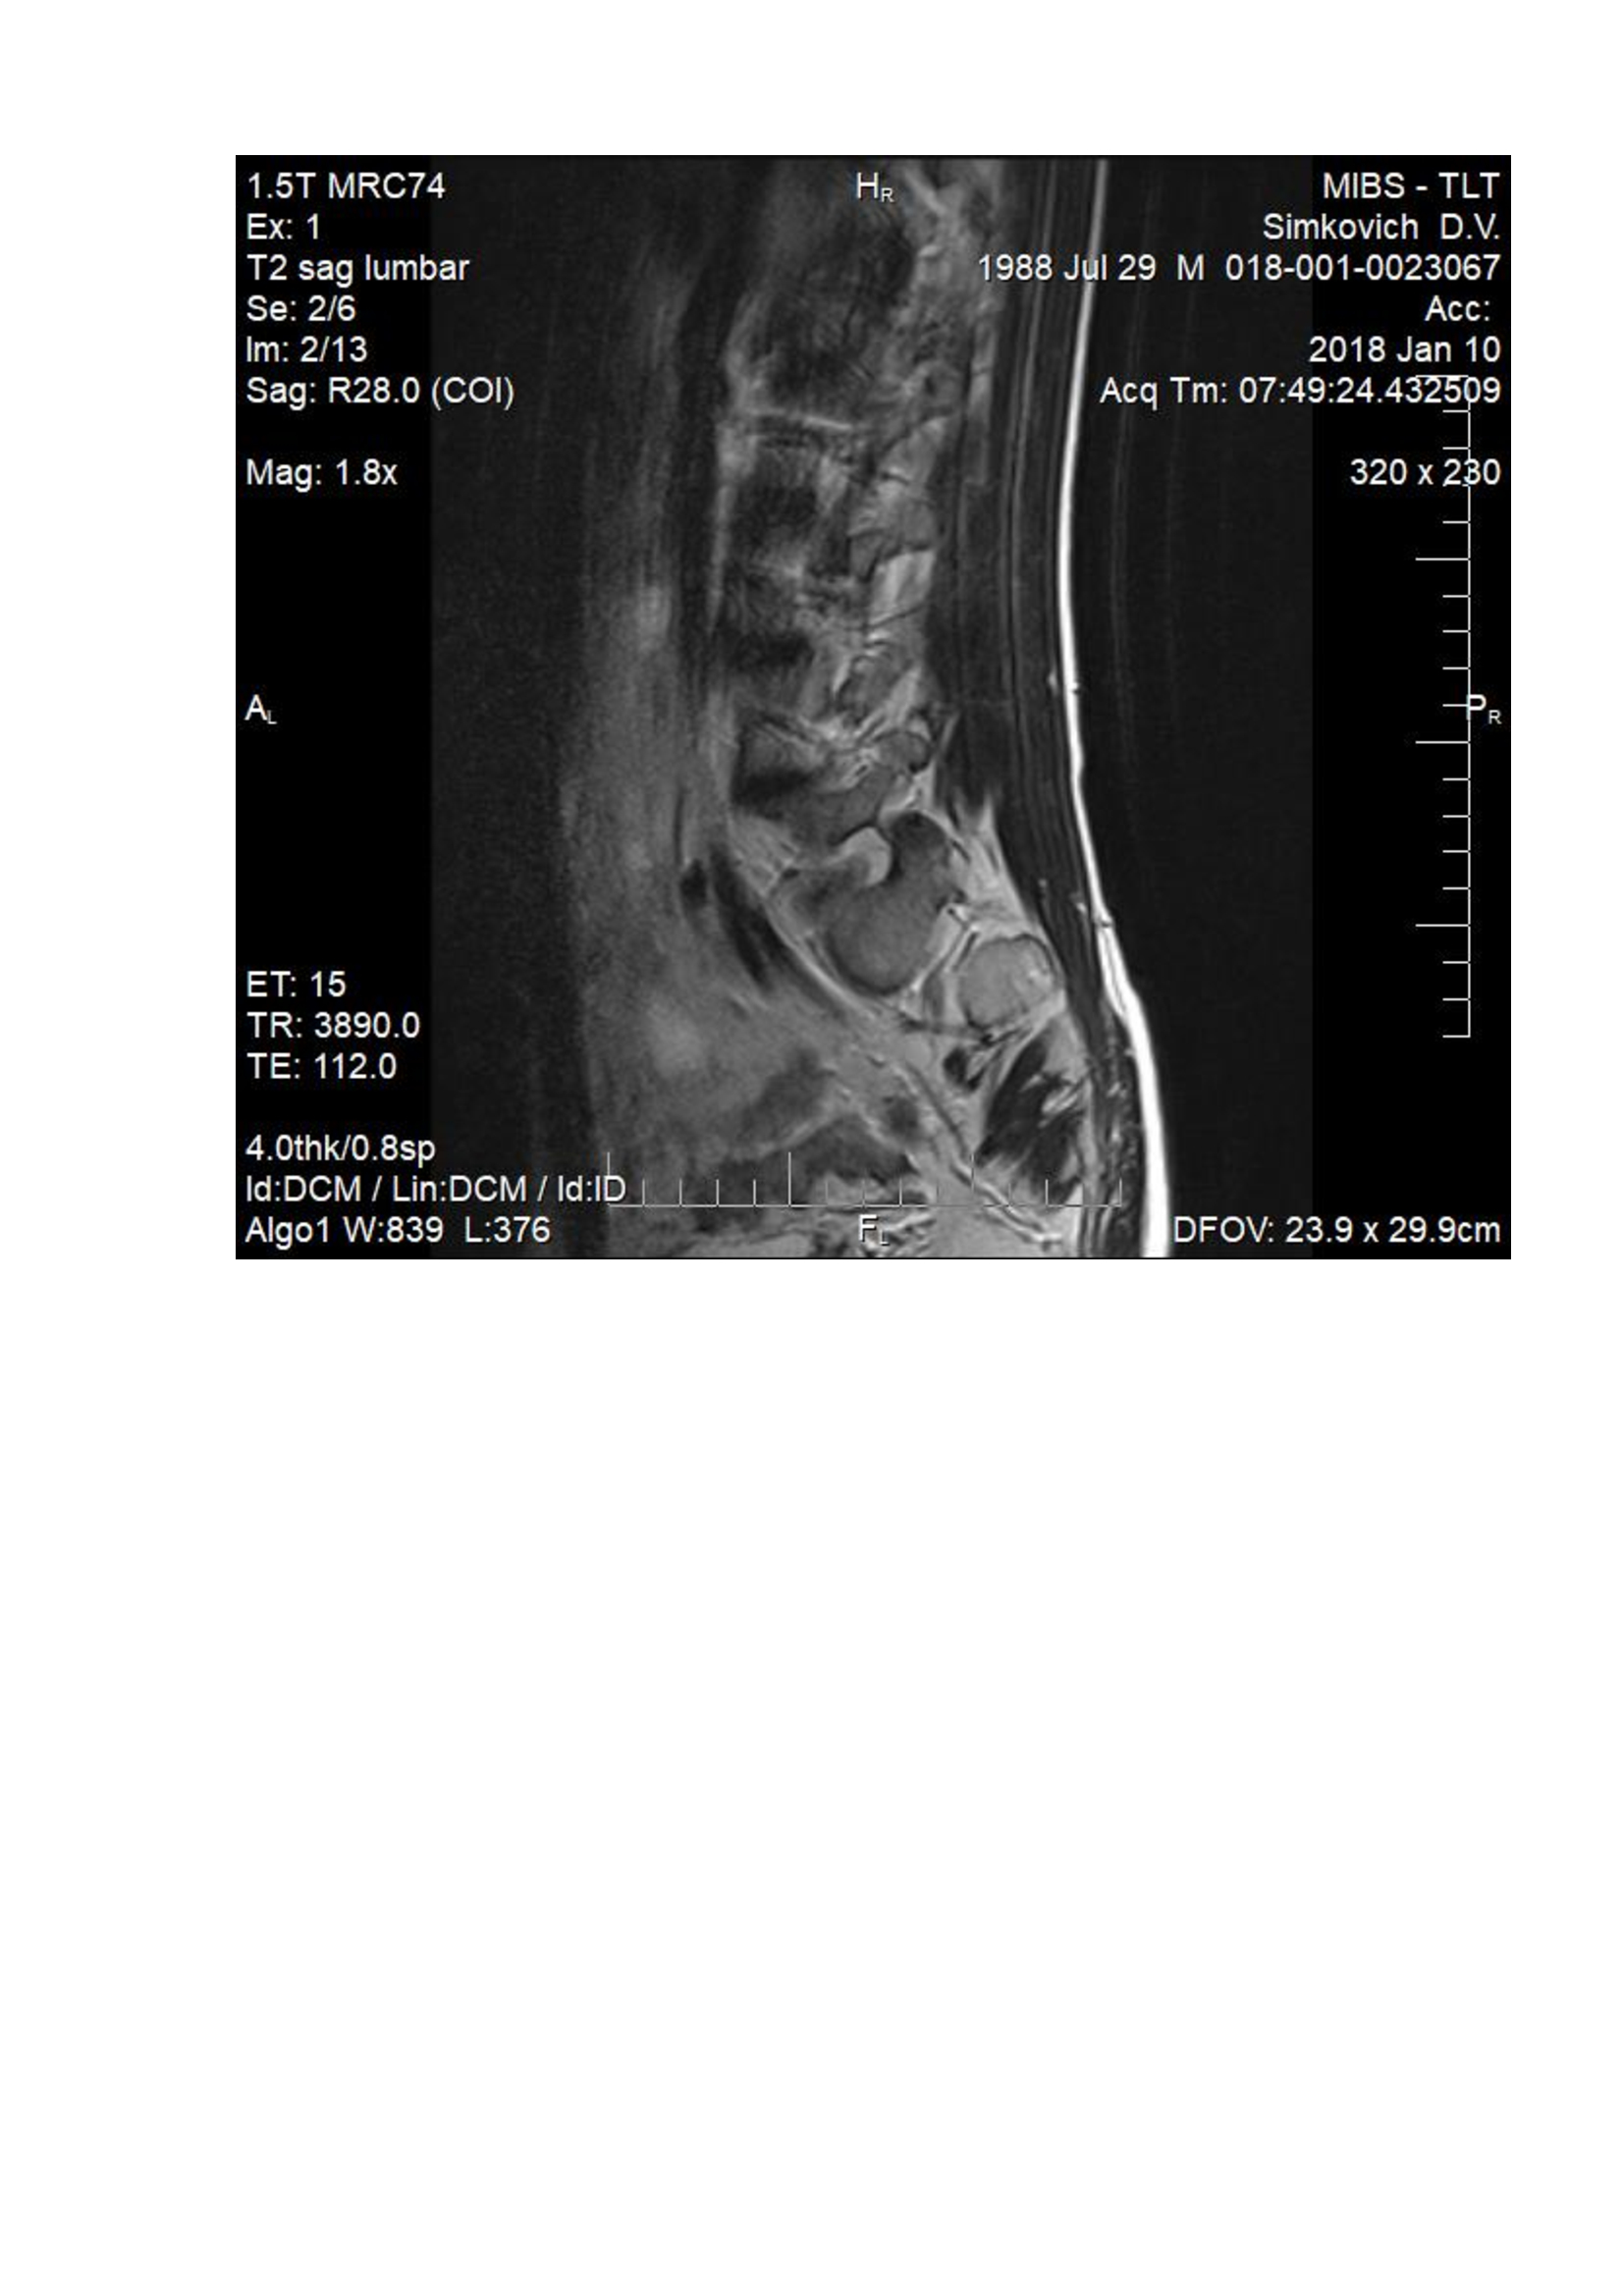

На данный момент болит правая нога, начала побаливать и левая, болит спина. При лежании на спине на ровной поверхности боль в спине проходит. Сделал МРТ. Неврологи нашего города ставят разные диагнозы, от фасеточного синдрома до нестабильности позвоночника. Консервативное лечение не помогает.

Посмотрите пожалуйста мои снимки.

a556ac9e464669c72f957fc9799ac181-8.jpg

a556ac9e464669c72f957fc9799ac181-5.jpg

a556ac9e464669c72f957fc9799ac181-1.jpg

Здравствуйте! судя по снимкам -грыжа удалена. Для определения формирования рубцово-спаечного процесса - мы делаем мрт с в/в контрастом, для определения нестабильности - обычный рентген с функциональными пробами, для определения степени поражения нерва ЭНМГ нижних конечностей. Далее становится понятно в какую сторону двигаться.